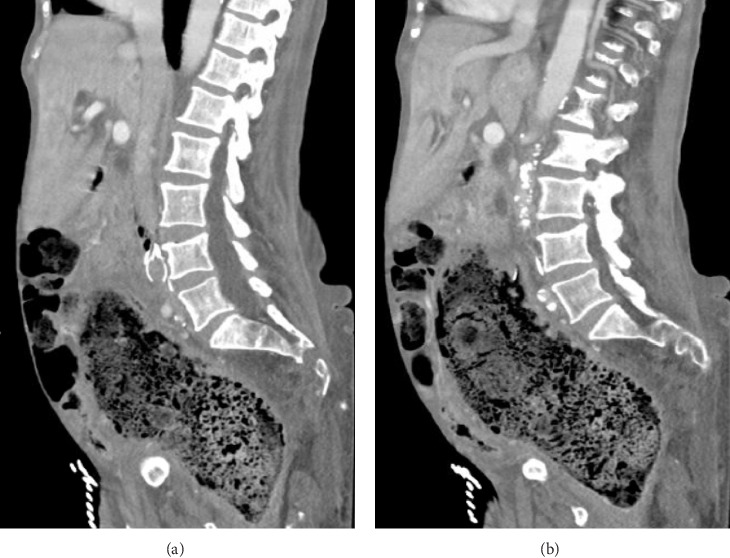

瘘管形成是解剖部位之间的连接,本质上是异常的。各种病因和相关结构存在这些异常发展。血管和肠系统之间的瘘管是罕见的。当存在时,解剖上的接近是决定涉及哪些结构的主要因素。主动脉肠瘘累及食道、十二指肠和小肠是众所周知的,胃也在罕见的情况下累及。瘘累及下腔静脉(IVC)和肠系统,也见过胃、小肠和胸内结肠介入手术后的瘘。我们报告了一位82岁的女性,她患有多种合并症,包括阿片类药物依赖、慢性便秘、下肢深静脉血栓形成、上消化道出血和下腔静脉滤器依赖,她出现了一个独特的问题。她的主诉是非特异性的,但最终诊断为下颌骨和乙状结肠之间的瘘管形成。本文所述的结肠瘘是文献中报道的第一例腹腔内瘘。

Fistula formation is a connection between anatomic locations that is intrinsically abnormal. A variety of causative etiologies and involved structures exist for these anomalous developments. Fistulas between vasculature and the enteric system are rare. When present, anatomical proximity is the dominant factor in determining which structures are involved. Aortoenteric fistulas involving the esophagus, duodenum, and small bowel are well-known with the stomach also being involved in rare instances. Fistulas involving the inferior vena cava (IVC) and enteric system have also been seen with the stomach, small bowel, and intrathoracic colon following an interposition each represented in reported cases. We present a case of an 82-year-old female with multiple medical comorbidities including opioid dependence, chronic constipation, recurrent lower extremity deep venous thrombosis, recurrent upper gastrointestinal (GI) bleeding, and IVC filter dependence who developed a unique problem. Her presenting complaints were nonspecific, but ultimately a diagnosis of fistula formation between the IVC and sigmoid colon was made. The colocaval fistula described here is the first intraperitoneal case to be reported in the body of literature.